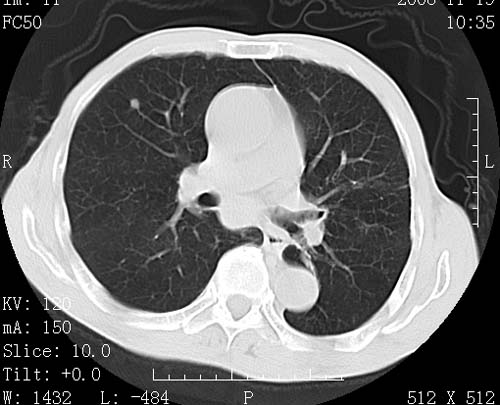

标题: CT16691:m 67 胃镜确诊食管下段及贲门癌 [打印本页]

标题: CT16691:m 67 胃镜确诊食管下段及贲门癌

术前查体,双肺部结节是转移?结核?请点评

1)符合食管癌表现。2)两肺及纵隔淋巴结多发性转移瘤。3)左肺上叶舌段及两肺下叶炎症感染。

食管癌伴双肺转移,评述:肺部毛细血管网丰富,全身血液均快速流经肺部,癌细胞容易过滤定植,形成转移瘤,影象特点为以毛细血管末梢为中心的结节灶,边缘光滑锐利,少见有中心空洞着,不同来源的转移瘤可有各自特点,如甲状腺癌为双肺弥漫性微结节,本例有原发灶,双肺影象灶典型,左肺舌段条带状网格样伴胸膜天幕征,可视为癌性淋巴管炎。